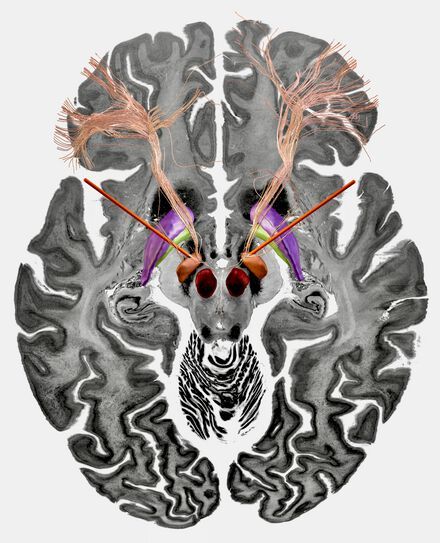

Affected brain circuits in Parkinson’s disease (green), dystonia (yellow), Tourette’s syndrome (blue), and obsessive-compulsive disorder (red). Inset: the optimal target areas for deep brain stimulation in the basal ganglia.

This raised the question of how such a small nucleus, only about one centimeter long, could be an effective target for symptoms of such different brain dysfunctions. To investigate this question, the team analyzed data from 534 DBS electrodes implanted in 261 patients across the globe. Of this cohort, 70 patients were diagnosed with dystonia, 127 with Parkinson’s disease, 50 with OCD, and 14 with Tourette’s syndrome. Using software developed by the team, the researchers reconstructed the precise location of each electrode. Computer simulations were then used to map neural tracts that were activated in patients with optimal or suboptimal treatment outcomes.

Using these results, they were able to identify specific brain circuits that had become dysfunctional in each of the four disorders. They were associated with the relevant regions of the frontal part of the brain that play an important role in motor functions, impulse control, and information processing. “The circuits we identified partially overlapped, which to us implies that the malfunctions reflected in the symptoms studied are not wholly independent from each other,” says Barbara Hollunder, a PhD fellow at the Einstein Center for Neurosciences at Charité and the first author of the study.

This means that as the first step, the researchers have succeeded in localizing the exact networks in the forebrain and midbrain that are crucial to treating Parkinson’s disease, dystonia, obsessive-compulsive disorder, and Tourette’s syndrome. Applying this same approach across disorders with different symptoms gradually yields a map that denotes how specific brain circuits are associated with certain symptoms. “By analogy to the terms ‘connectome,’ which describes a comprehensive map of all neural connections existing in the brain, and ‘genome,’ which is used for the full set of genetic information found in an organism, we have coined the term human ‘dysfunctome.’ One day, we hope the dysfunctome will describe the entirety of brain circuits that may typically become dysfunctional as a result of network disorders,” Hollunder explains.